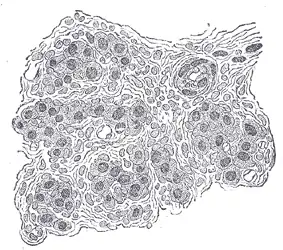

![]() Section of part of human carotid body. Highly magnified. Numerous blood vessels are seen in section among the cells. | |

The carotid body is a small cluster of peripheral chemoreceptor cells and supporting sustentacular cells situated at the bifurcation of each common carotid artery in its tunica externa.[1][2]

The carotid body is made up of two types of cells, called glomus cells: glomus type I cells are peripheral chemoreceptors, and glomus type II cells are sustentacular supportive cells.

- Glomus type I cells are derived from the neural crest.[4] They release a variety of neurotransmitters, including acetylcholine, ATP, and dopamine that trigger EPSPs in synapsed neurons leading to the respiratory center. They are innervated by axons of the glossopharyngeal nerve which collectively are called the carotid sinus nerve.

- Glomus type II cells resemble glial cells, express the glial marker S100 and act as supporting cells.